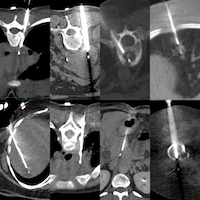

55-yrs old treated buccal ca with focal soft tissue and uptake on a follow-up PET in the left posterolateral maxillary sinus wall was referred for a CT guided biopsy.

Findings: Focal uptake posterolateral maxillary sinus wall

Gun: 18G Cook, 10 mm throw, short

Position & Approach: Rt lateral decubitus, straight down, infrazygomatic

Diagnosis: Squamous cell carcinoma, recurrence